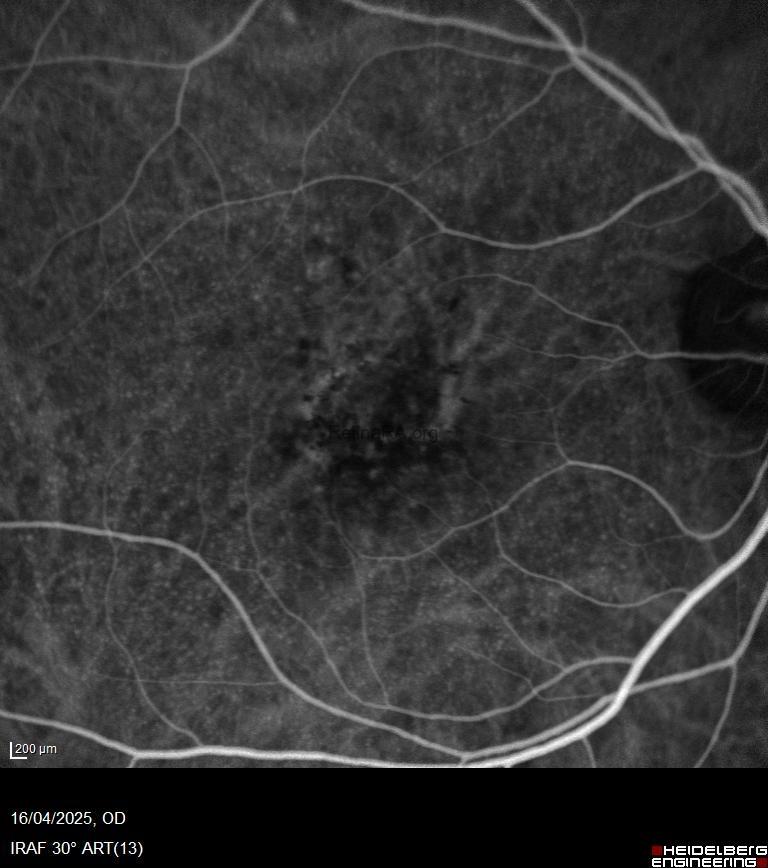

* Fundus Fluorescein Angiography (FFA/FAG):

Exhibits a characteristic “starry-sky” or “milky-way” pattern, with numerous, small, round hyperfluorescent lesions appearing during the intermediate or arteriovenous phase.